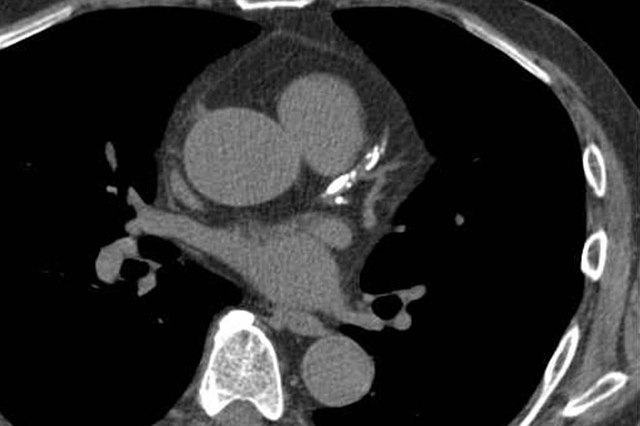

복부 CT(Computed Tomography, 전산화단층촬영)는 복부 내 다양한 장기 및 구조를 세밀하게 영상화할 수 있는 강력한 진단 도구입니다. 일반 엑스선 사진이나 초음파로는 식별이 어려운 연부조직, 혈관, 내부 병변까지 고해상도로 확인할 수 있기에, 복통·복부 팽만감·체중 감소·비정상 혈액검사 수치 등 다양한 증상의 원인을 찾는 데 자주 활용됩니다.

- CT는 X선을 여러 각도에서 촬영하고 컴퓨터로 조합해 단면 영상을 만드는 방식입니다.

- 조영제(contrast)를 정맥 내 주사하거나 경구 투여하면 혈관이나 장기의 대비가 향상되어 병변 식별에 유리합니다.

- 영상은 장기 구조, 밀도 변화, 병변의 크기와 형태, 주변 조직과의 경계 등을 보여 줍니다.

- 복부 CT는 복부와 골반을 포함한 넓은 범위를 한 번에 관찰할 수 있어, 내부 장기뿐 아니라 복막, 혈관계, 림프계 병변 탐색에도 유용합니다.